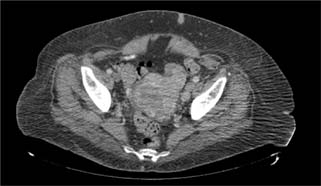

The patient’s medical and surgical history was unremarkable except for insulin independent diabetes mellitus. A left-sided abdominal mass was palpable on physical exam. Further evaluation revealed no evidence of distant metastatic disease on CT imaging of the head, chest x-ray, recent CT chest, or CT abdomen and pelvis. Magnetic resonance imaging of the abdomen, obtained approximately 1 month prior to her surgery, did not reveal any evidence of left renal vein involvement. After extensive counseling and a thorough discussion of the risks involved and the benefits, she opted for surgical extirpation of her locally advanced renal mass and regional lymphadenopathy. She underwent an open left radical nephrectomy, total abdominal hysterectomy with bilateral salpingo-oophorectomy, and retroperitoneal and pelvic lymph node dissection. Intraoperatively, the mass was found to be large and bulky, extending toward the pelvis and invading the local structures. The ascending colon was reflected medially, at which time the mass was noted to be involving part of the mesentery, which required resection. Once the hilum was controlled, the mass was dissected down toward the pelvis and was noted to be involving the uterus and the bilateral ovaries. A supracervical hysterectomy with bilateral salpingo-oophorectomy was performed. The left gonadal vein with tumor thrombus was mobilized and the mass was dissected off the lateral abdominal wall, which allowed the whole specimen to be elevated en bloc until it was completely free. A retroperitoneal and left pelvic lymph node dissection was completed, and all specimens were sent for pathologic examination. Estimated blood loss was 750 mL, and there were no intraoperative or postoperative complications. The patient had an uneventful 5-day hospital course and was discharged to a subacute rehabilitation facility. Upon further review of the abdominal and pelvic CT scan, there was a heterogeneous appearance of the uterus, which had been assumed to be related to fibroids (Figure 2).

Figure 2: Axial view of computed tomography of the abdomen and the pelvis revealing a heterogeneous appearance of the uterus.